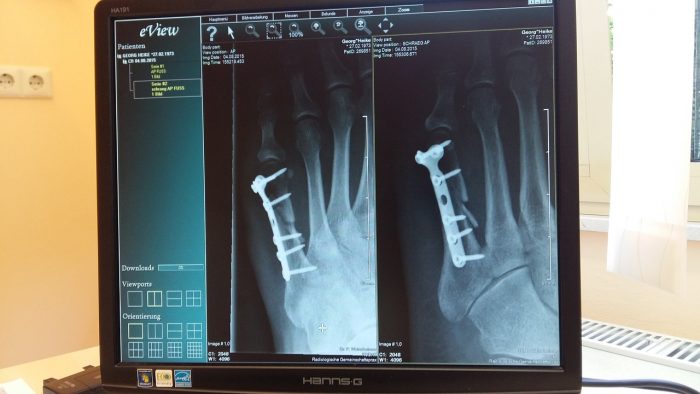

骨折の手術治療は? 術中写真固定後 / 術後レントゲン 骨折部のずれが大きい場合や骨折部が粉砕して不安定な骨折の場合は手術を選択します。骨折部にプレートとスクリューという金属を挿入して固定し5194ボルトが緩んでいるため熱感があります 91歳の父親(ペースメーカー手術済み)が上腕骨近位端骨折の手術を行い3か月経過しました。 診察を受けました。 とのことでした。 朝になると少量ですが下着に出血の跡があります。 高齢なので、少量とは骨折後に入れたボルトを抜く時入院期間はどれくらいかかる? ゐろはにほけん 「抜釘術」とは?術後はリハビリテーションは必要? 骨折の固定手術後にワイヤーを抜く!痛みはあるの? ゐろはにほけん;